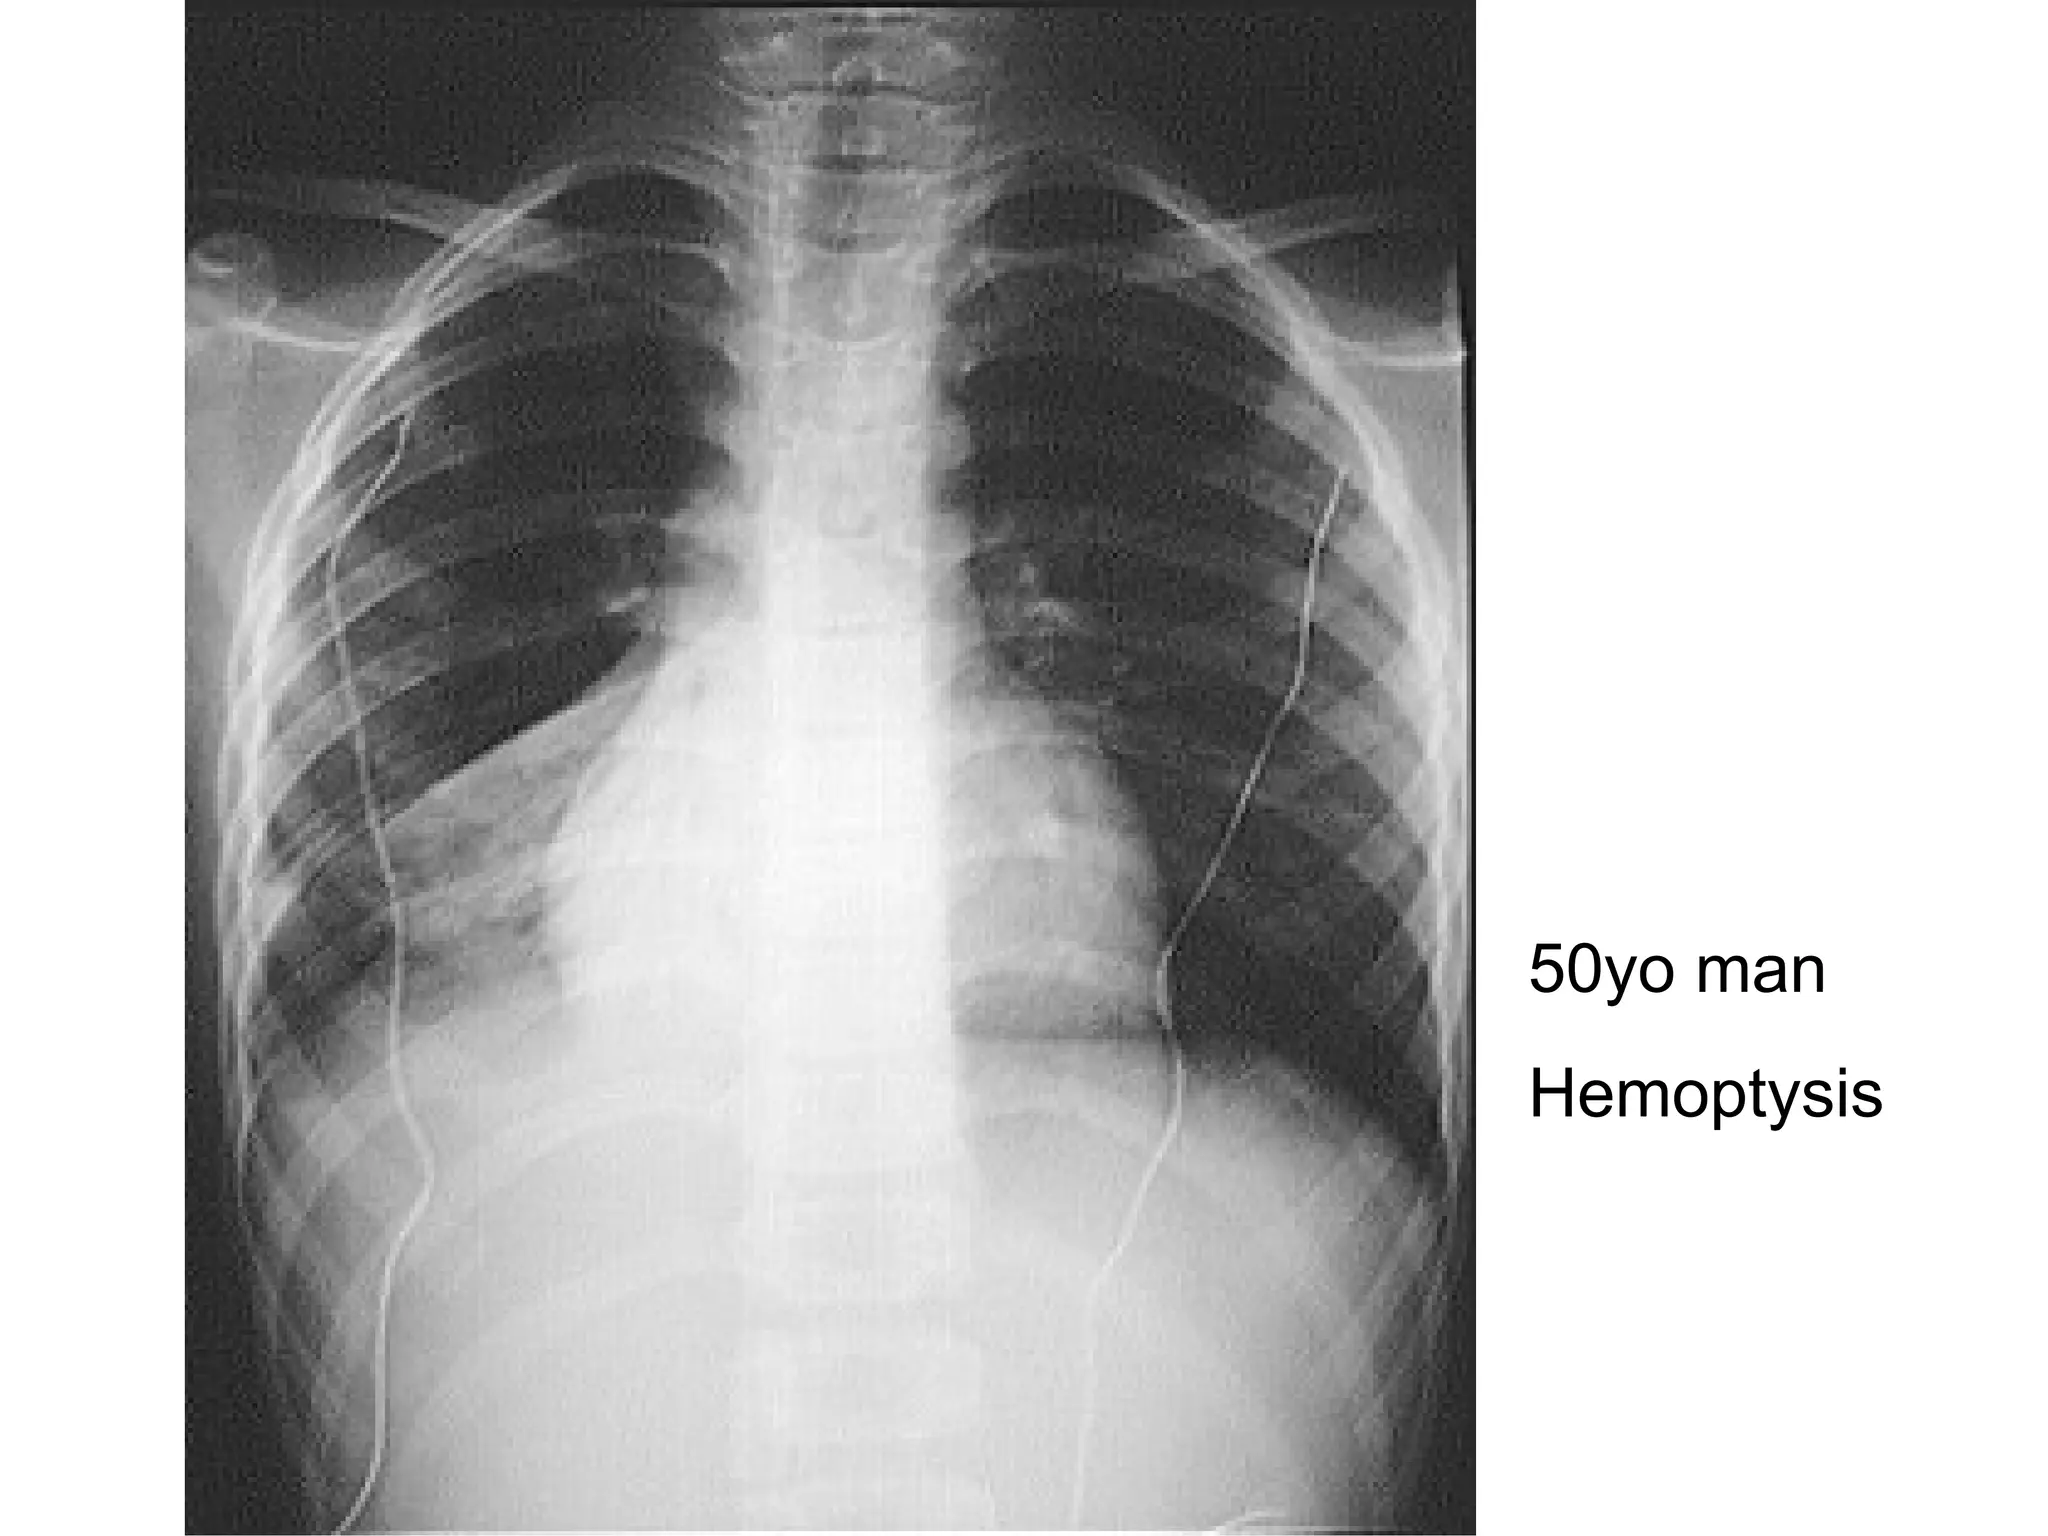

50yo man  Hemoptysis

CXR- opacity Describe? Opacity at R lower zone Mediastinal shift Causes? Bronchogenic carcinoma TB (tuberculoma) pneumonia

CXR- opacity Describe?Opacity at R lower zone Mediastinal shift Causes? Bronchogenic carcinoma TB (tuberculoma) pneumonia